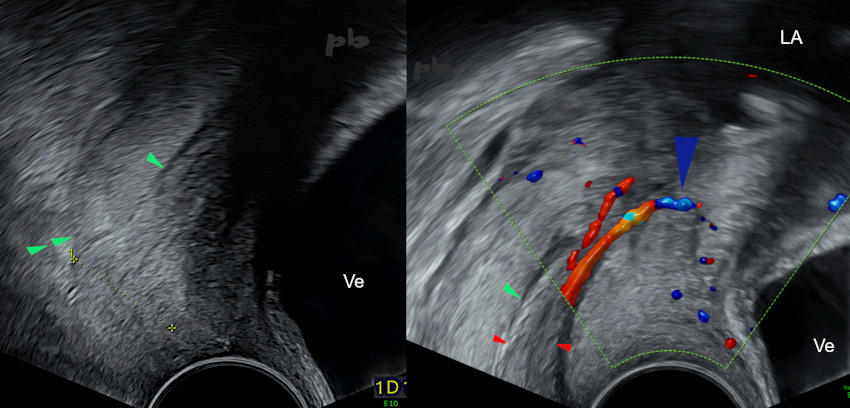

9 – Polype endocervical

(même patiente que 8)

Echographie endovaginale – coupes sagittales centrées sur le col.

- à gauche : polype (entre les croix) accouché par le col. Lèvre postérieure (►►) et face postérieure du canal cervical (►).

- à droite : polype (►) et pédicule (►) s’implantant en avant vers l’orifice interne du col.

Ve = vessie

LA = liquide amniotique